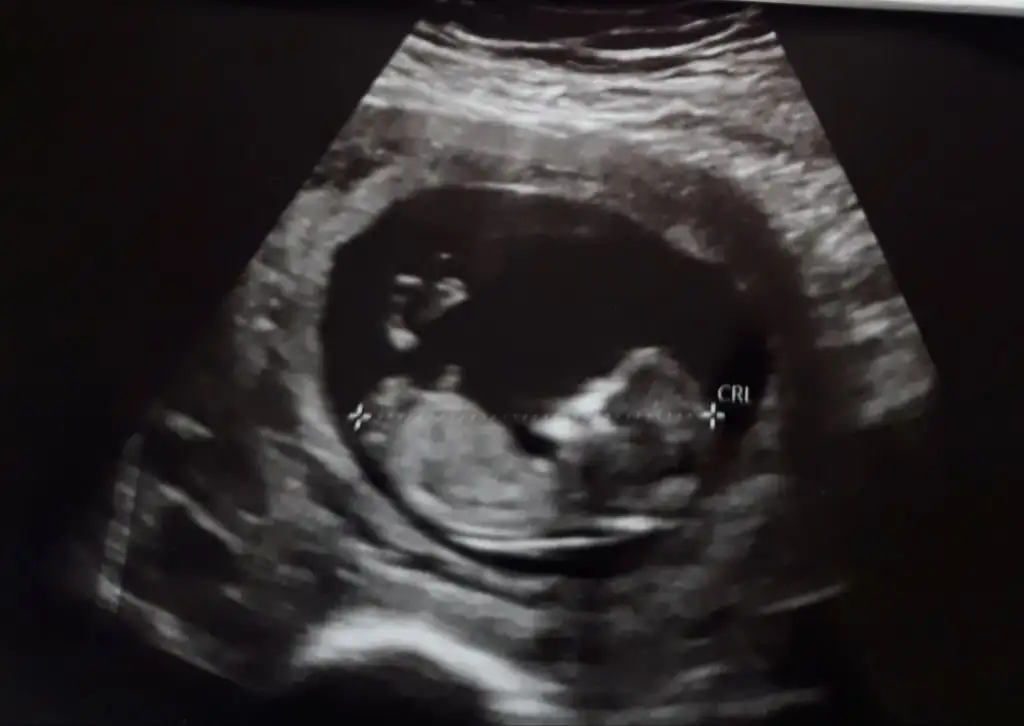

Kiz gibi sanki emin olamadımEki Görüntüle 2977845 İkra Meyra bizede bakabilir misin 12+4

Kız görünüyorCinsiyete bakabilir misinIkra meyra 11+4 günlük sizce ne olabilir l

Erkek gibi sanki12+1 fikri olan var mı?

Nubu gözüküyor mu acaba ben anlayamıyorum yoksa başka bir yerden mi anladınız kız oldugunuKız görünüyor

Erkek gibi nubu dik görünüyor12 haftalik usg yorum yaparmisiniz rica etsem